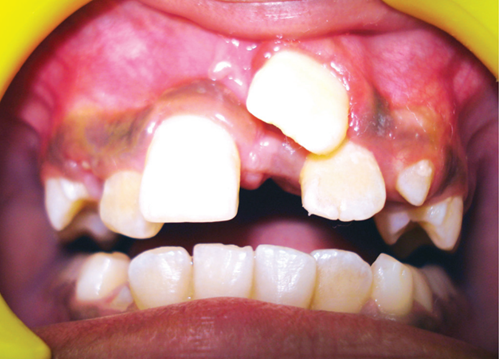

R21 chưa mọc, R11 đã mọc (a), Răng thừa (b), R22 (c) (b)Răng thừa thứ nhất, (a) răng thừa thứ 2, (c) R21 ngầm chưa mọc Phẫu thuật lật vạt:(a) răng thừa thứ 1, (b) R21 ngầm, (c) R22

image 20231218155055 19 502x340

Răng thừa thứ 1đã được nhổ Bộc lộ răng thừa thứ 2 Hình ảnh 2 răng thừa

Hình ảnh sau phẫu thuật 6 tháng, R21 đã mọc lên sau khi loại bỏ 2 răng thừa

Hình 4: Minh họa cho phẫu thuật lấy răng thừa đơn thuần ở một bé trai 9 tuổi